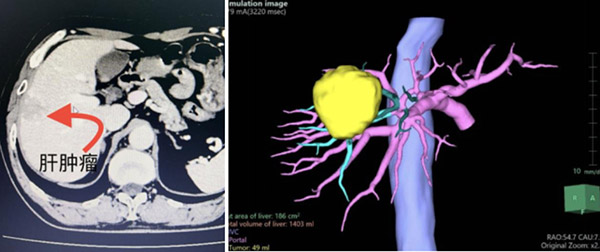

直径4厘米的肿瘤,不偏不倚长在了曾被视为手术“禁区”的肝脏顶部(S8段),这里血管、神经密集,暴露困难、大出血风险高,那么该如何既治愈疾病又保证病人的安全?近日,沈阳市第六人民医院(沈阳市肝胆外科医院)院长徐进教授亲自主刀,带领普外二科王玉文团队参照国际标准,联合应用荧光腹腔镜技术和术中超声完成一例肝S8段切除,安全、精准、高效地为病人解决了疾病困扰。这次勇闯“禁区”的成功,标志着市六院应用腹腔镜实施复杂的肝胆胰微创手术已成为常规化,医院对大型手术的承接能力以及微创化、高精准的诊疗技术,也达到了地区的领先水平。

42岁的丁先 生患慢性乙肝多年,最近体检发现肝脏顶部(S8段)占位性病变、甲胎蛋白升高,这些都与肝癌相关。于是他赶忙到家附近的医院接受了增强CT和增强磁共振检 查,结果显示为肝细胞癌,病灶直径达4厘米。作为一个老沈阳人,丁先生果断来到作为沈阳市肝癌诊治中心的市六院,向国内著名肝胆胰外科专家徐进院长寻求治 疗。

通过一系列专业、完善的检查,徐进院长明确了肝癌的诊断。“早期诊断、早期采用以手术切除为主的综合治疗,是提高肝癌病人长期治疗效果的关键。从病人角度考虑,损伤小、恢复快的微创腹腔镜肝切除无疑是最佳选项,但由于丁先生病变的体积大,所在位置血管、胆管和神经密布,极易发生术中大出血,甚至危及生命,这给医生的操作和技术提出了非常高的要求。”在看过肝部影像、计算机3D模拟图像后,徐进院长说道。